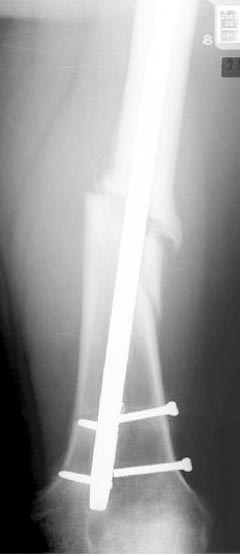

Из истории болезни: два года назад проперирован по поводу 3А открытого перелома бедра, травма на работе в результате "стена упала на него". Сопутствующая травма: Закрытая травма черепа, перелом голеностопного сустава (прооперериван) и перелом плеча (консервативное лечение)

Лечение бедра - ургентное оперативное лечение антеградным с минимально рассверливанием, фиксацией с минимальным диаметром штифта и плюс irrigation and debridment и с закрытием поперечной до 10 см раны на уровне перелома в день поступления.

После трех дней начались выделения из ран которые промывалась в палате и рана постепенно закрылась в течение нескольких месяцев. Эмпирически получал 6 недельний курс антибиотика Vancomycin внутривенно.

Снимки представлены: 1 мес; 3 мес; 1 год; 2 года, предоперационные и ротационная КТ грамма

Деформация:

Вальгус- 17 градусов

Рекурватум 5 градусов

Укорочение 2.5см

Ротационно 22 градусов внутренная

Смещение диафиза по поперечнику 75%

Операцию провели в два этапа, сперва удалили штифт, рассверливание римером на пару мм большего диаметра, определение чувствительности на анаэробную и аэробную культуру (где исследования показали негативный результат чувствительности), через дней десять - начали аппаратную фиксацию.